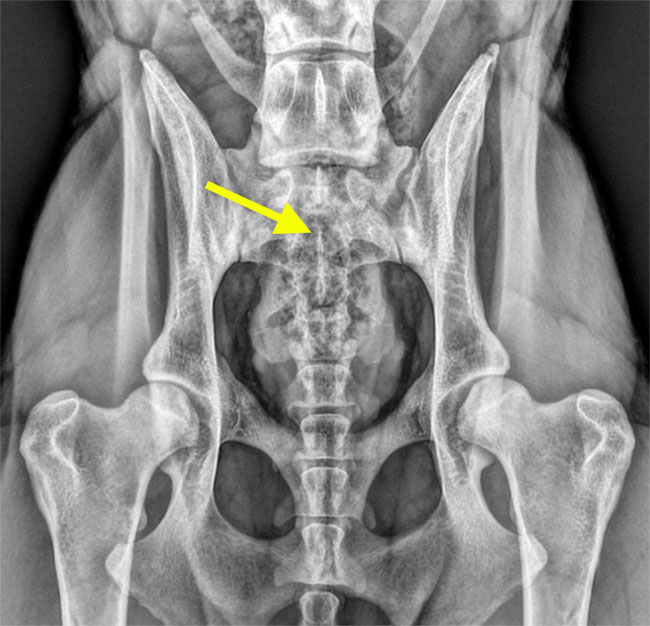

Riassunto degli esami radiografici dell'anca (HD) e dei gomiti (ED) nei cuccioli provenienti dal mio allevamento.

Il mio lavoro non sarebbe possibile senza il sostegno e la collaborazione dei proprietari dei miei cuccioli. Sottoporre i cani all’esame radiografico ufficiale per la displasia dell’anca e del gomito è un gesto importante e di grande valore. A tutti voi che con impegno e fiducia sostenete il mio lavoro va la mia sincera e profonda gratitudine.